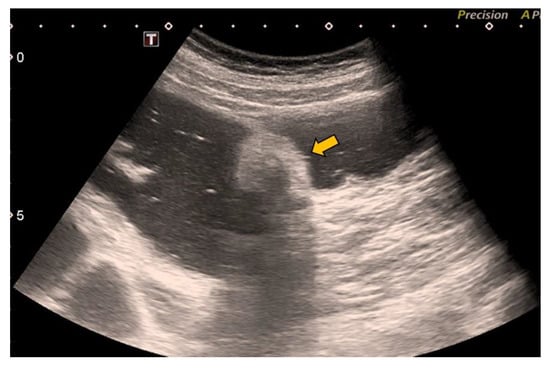

In our case, it was possible to follow up on the lipoma during biannual OCs performed because of her personal history of polyposis. Initially, it was proposed that abdominal-CT scans (Figure 1 and Figure 2) should be performed the year after each OC. This way, the size of the lesion could be monitored, and the degree of local infiltration could be determined. After the first abdominal-CT follow-up, to avoid exposure to radiation, HS (Figure 3) was included as an alternative to abdominal-CT. In the subsequent follow-up, in addition to the biannual OCs, two hydrocolonic ultrasound scans (without cleansing preparation) and one abdominal-CT scan were performed. During the seven years of follow-up, the lipoma remained stable, and the patient remains asymptomatic.

Figure 2.

Coronal CT reconstruction of the abdomen with intravenous and oral contrast showing the colonic lipoma (yellow arrow).

MR with fat saturation techniques can also be useful for detecting lipomas, but the detection of small lesions can be complicated [7]. The sensitivity of MR in the detection of fat composition is 100% [1]. Lipomas are easily distinguishable using abdominal-CT, as they appear as well-defined hypodense lesions between −40 and −120 Hounsfield units [36] (Figure 1 and Figure 2). The sensitivity of abdominal-CT in the detection of lipomas is 58–100%, and they have a characteristic image that looks like a “target sign” or “doughnut sign” [5,37]. Abdominal-CT is a very useful technique in urgent cases, but for follow-up, it presents problems due to the associated radiation. In addition, local infiltration can be difficult to exclude using abdominal-CT or MR [1].